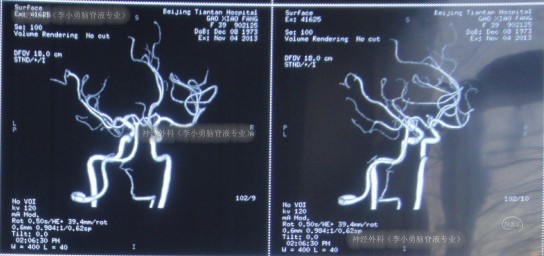

患者于2013年11月4日,突发剧烈头痛,难以忍受,前往北京某三甲医院进行头颅CT示蛛网膜下腔出血(图-1),随即进行头颅CTA检查确诊为右前交通动脉瘤(图-2)。

图-2:2013年11月4日脑CTA